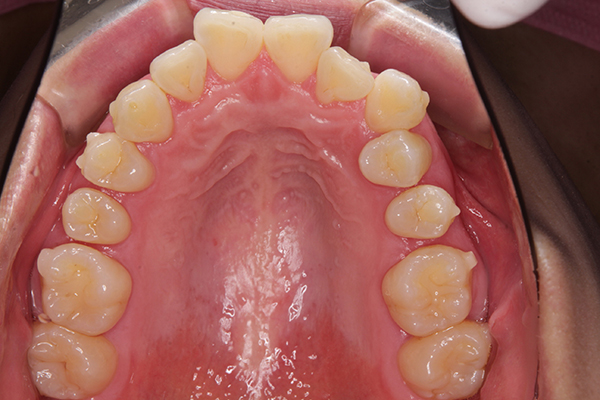

写真は、オルソパルスと、矯正開始から80日経過の口腔内写真です。

上の歯に隙間が空いていて、こうして見てみると面白いですね(笑)

下の歯の横の銀色のボタンは、顎間ゴムをひっかけるためのものです!